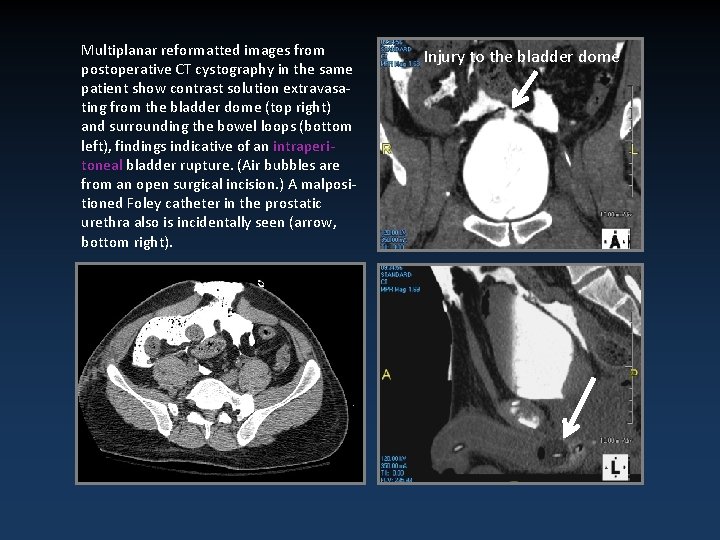

Multiplanar reformatted images from postoperative CT cystography in the same patient show contrast solution extravasating from the bladder dome (top right) and surrounding the bowel loops (bottom left), findings indicative of an intraperitoneal bladder rupture. (Air bubbles are from an open surgical incision. ) A malpositioned Foley catheter in the prostatic urethra also is incidentally seen (arrow, bottom right). Injury to the bladder dome